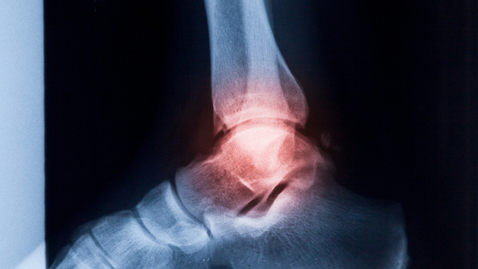

Dr. Miller: I'm here today with Dr. Alexej Barg and he is an orthopedic surgeon here at the University of Utah. He specializes in foot and ankle problems. Alexej, ankle sprains are very common and occur frequently among adolescents and kids who are playing sports. Under what circumstances should one go receive additional attention after spraining an ankle to make sure that they haven't fractured the ankle?

Dr. Barg: The ankle sprain is for sure the most common injury in the United States. This is actually also the most common sports injury. More than every 10th patient who is showing up in the emergency room is coming to the clinic because of the ankle sprain. Of course, you cannot just do in every patient without seeing this patient, just the routine radiograph assessment.

If the patient does present with a swelling with some hematoma, that means some color change, on the medial and/or lateral side, there's definitely need to perform or to do the radiographs, the X-rays to exclude a bone fracture.

Dr. Miller: What about if right after the ankle is sprained that they cannot weight bear? Does that make a difference? I've heard that sometimes, if the person who sprains their ankle is not able to put weight on that foot for a period of time right after the injury, they should receive an X-ray.

Dr. Barg: Usually, right after the injury, almost everybody who has ankle sprains cannot bear weight. I would definitely wait a couple hours. Usually, those patients have some substantial pain relief within four to six hours after the injury, especially if they do elevate the foot, if you do the cooling of the injured ankle.

If they still experience a very severe pain after six hours so they cannot walk on it at all, there is definitely an indication or the need to do the radiographs. Another question is if the patient continues having pain two or three weeks after the injury, it doesn't matter whether it was a mild injury, they need an x-ray. They should go to the clinic and, first of all, the orthopedic surgeon should take a look at it.

Dr. Miller: You probably need an X-ray or should get an X-ray and seek attention for that. If you can't weight bear immediately after, that doesn't necessarily mean that you have a fracture, but if that persists beyond a day or 12 hours to a day, then you probably need an X-ray. Even if it's a mild sprain and you're still struggling with pain after a couple of weeks, then you need to seek attention for that and get radiographs to make sure you haven't had a fracture.